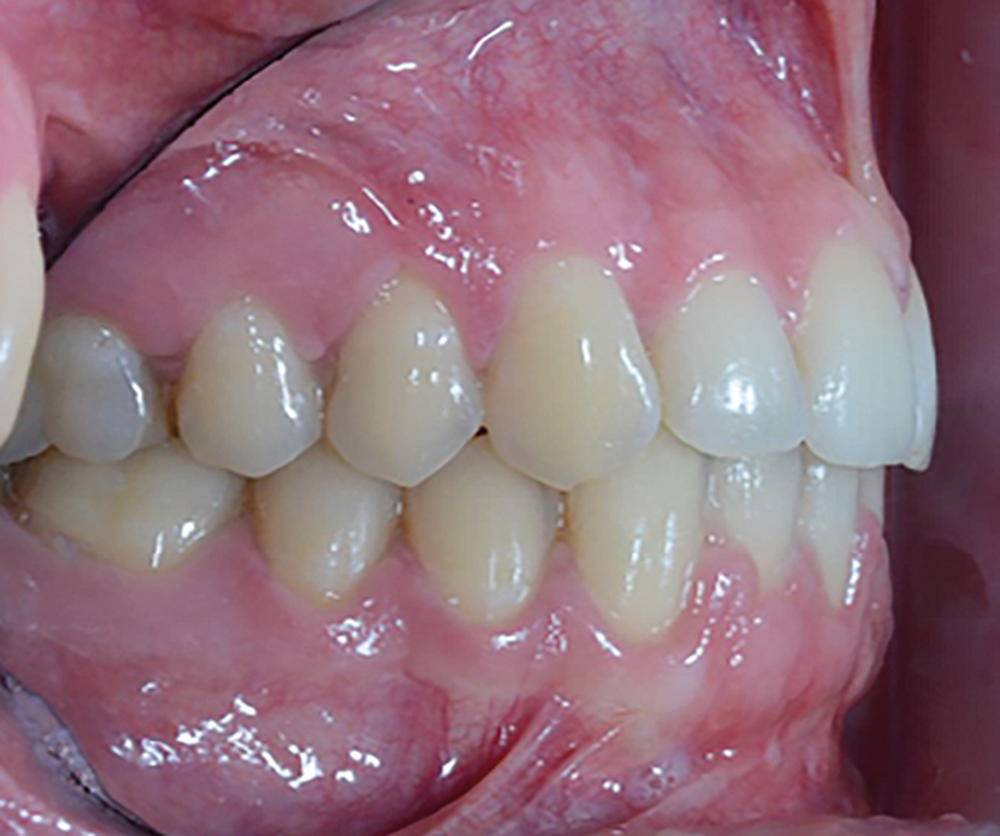

Le Pr Olivier Sorel insistera sur l’importance du respect des formes et des proportions anatomiques, pour éviter de voir apparaître, notamment chez les adultes, de très inesthétiques triangles noirs lors de la phase d’alignement (fig. 6a-b). Il présentera sa démarche diagnostique (évaluation de la forme des dents et de la dysharmonie dento-dentaire, fig. 7a-c) et l’intégration de la réduction amélaire proximale au plan de traitement, afin de s’assurer, en fin de traitement, la présence de papilles gingivales et donc d’un sourire harmonieux (fig. 8a-d).